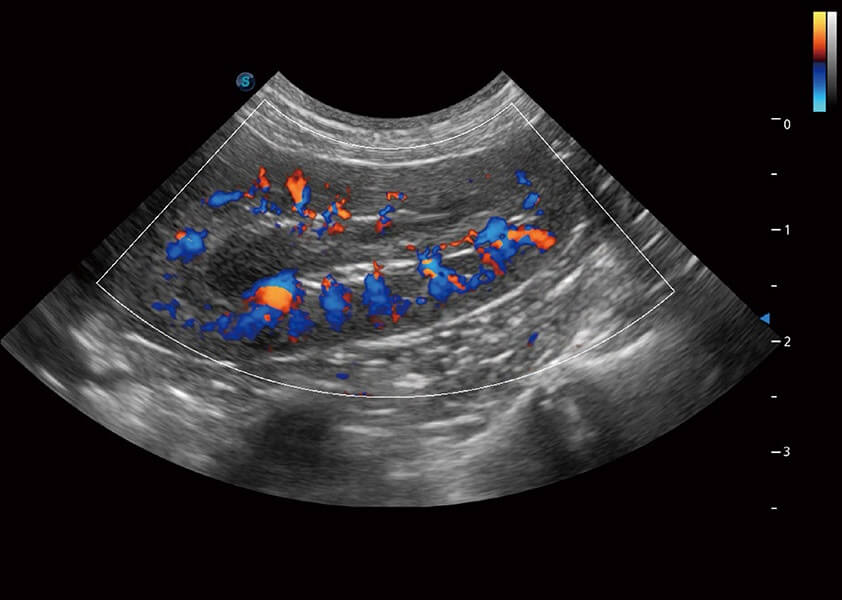

ProPet 60 作為一款高端臺式動物超聲設(shè)備,為動物醫(yī)生的日常診斷提供了一系列貼合動物臨床需求、解決臨床實(shí)際問題的高級成像功能。憑借全系列高清探頭,滿足醫(yī)生對腹部、心臟、生殖、淺表、肌骨等成像的所有需求,切實(shí)幫助您提升檢查效率,提高診斷信心。